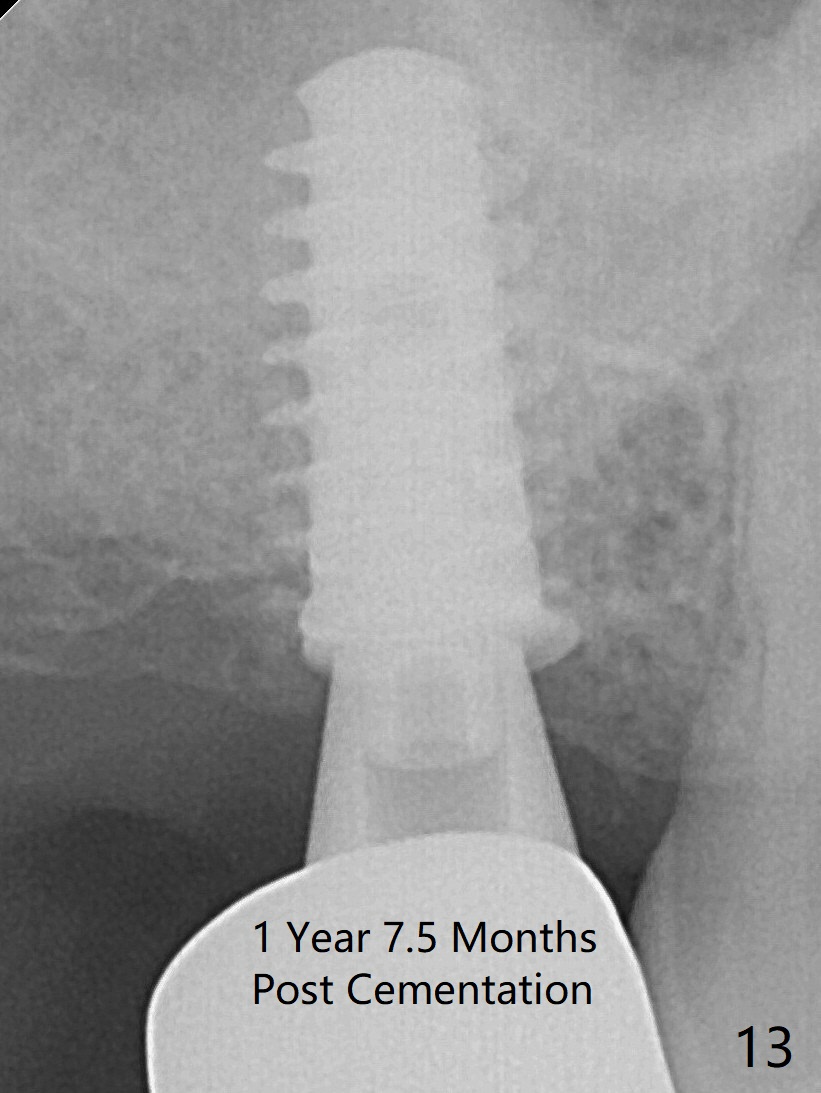

Five months post op, the healing abutment has mobility with light tenderness. The space between the bone and implant is larger than normal (Fig.10). The implant is stable with the healing screw 8 months postop (Fig.11). There is definitive sign of osteointegration 12 months postop (3 months post cementation, Fig.12). The final pair abutment is 5x4(4) mm. The patient is pleased to have the implant for 1 year 7.5 months post cementation (Fig.13).